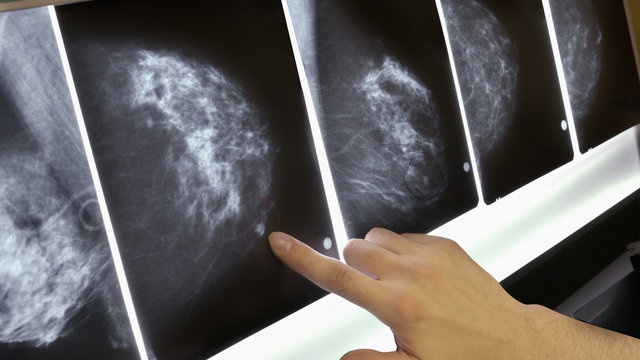

| Ung thư vú được nhận biết sớm có tỷ lệ khỏi rất cao. Ảnh: Gettyimages. |